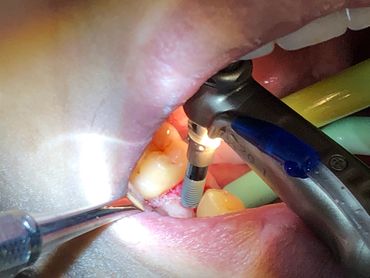

All implant drivers are provided with

indexer (Exact) markings to guide

implant installation, according to

prosthetic rehabilitation